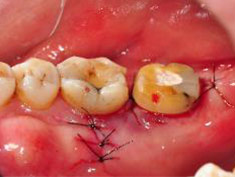

J圖為術後一級縫合。

K 圖為術後一級縫合。